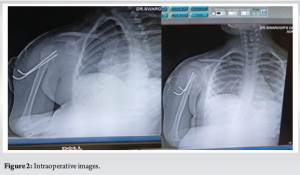

Under general anesthesia, closed reduction was achieved using the Kapandji and Jyoctiky maneuver, and the fracture was stabilized with percutaneous K-wires under fluoroscopic guidance (Fig. 2). Post-reduction alignment was satisfactory, with complete varus correction and mild residual translation (Fig. 3). The patient’s arm was immobilized with Dynaplast strapping (Fig. 4).

Follow-up at 2 weeks included Dynaplast removal, initiation of gentle pendulum exercises, and progressive rehabilitation. By 3 months, the patient had nearly full range of motion, with radiographs confirming complete healing without growth disturbance. At 6 months, she had returned to pre-injury activities, including sports, with no pain or functional limitations.